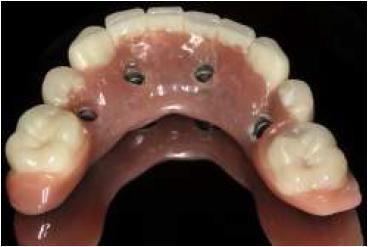

Al tercer día se realizó la instalación con torque manual y ajuste oclusal (figs. 13,14,15,16).

A los 10 días, luego de la cirugía, se citó a la paciente a control para realizar la retirada de la sutura11; se dio torque a los tornillos protésicos (10 N/cm) y se chequeó la oclusión nuevamente. Se ha seguido controlando a la paciente cada 6 meses, hasta cumplir 2 años desde la fecha de instalación de la aparatología, sin manifestar complicación alguna (figs. 17, 18, 19, 20, 21).